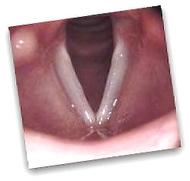

Throat cancer, especially stage 2, has the potential to come back. Though there may be no detectable signs of cancer currently, there is the possibility of cancer coming back in the future.

The risk of cancer recurrence is highest within the first 2-3 years after treatment completion, and markedly decreases after 5 years.

Typically if cancer has not come back after 5 years, the word "cure" may than be used, but even than, such patients are seen yearly for the rest of their life for cancer monitoring.